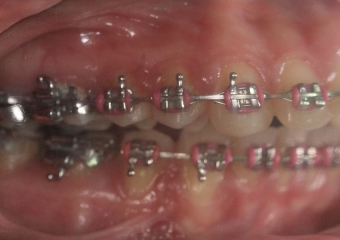

Mordida após a cirurgia